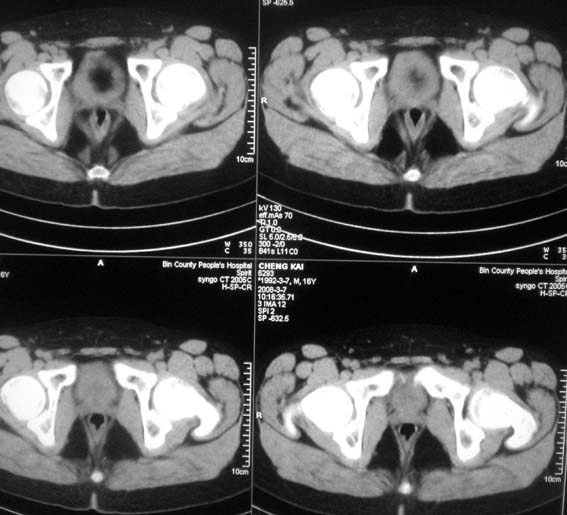

标题: CT12101:髋关节疼痛,请会诊。

男,16岁,髋部疼痛,发育延迟。

考虑:双侧髋臼发育不良性骨病。

双侧髋臼发育不良性骨病

双侧髋臼发育不良性骨病.股骨头早期坏死?

双侧髋臼发育不良性骨病(髋臼窝变浅,髋臼内上缘关节面毛糙)。